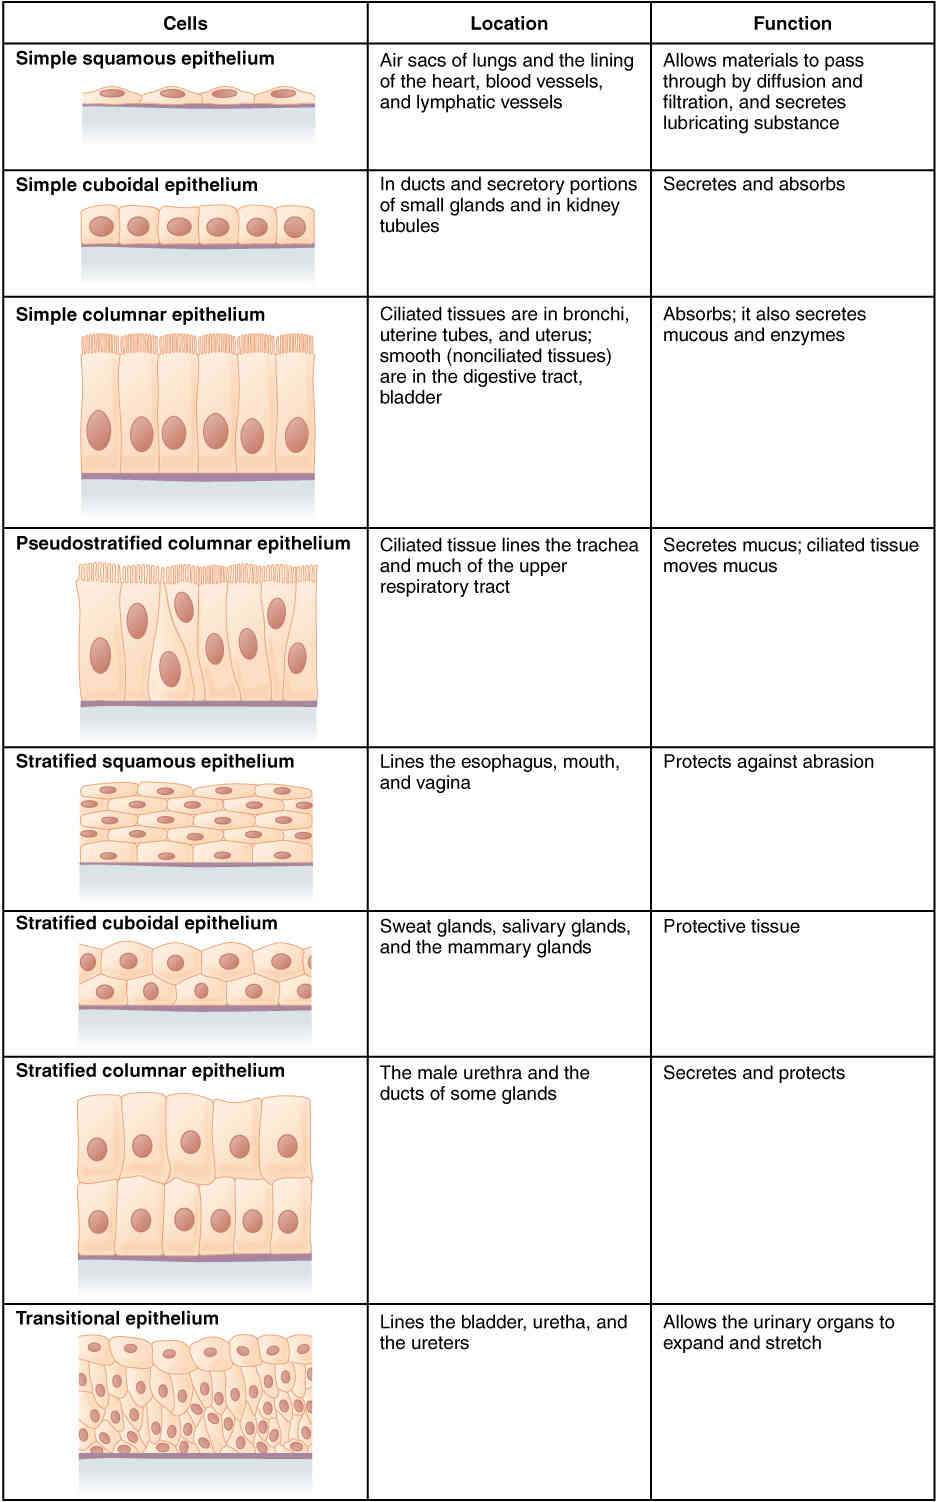

This page is under construction. For now, it is just a resource of the images found in the OpenStax Anatomy and Physiology Handbook. It wil slowly change into a revision tool. Each slide has a number. Use this to refer to the slide. When completed, it will have an unlabelled section, with labelled slides in parallel. On the unlabelled slides, write your answer and use the labelled slide to assess yourself. Keep track by also noting the number on each slide. Improvement at each attempt is important, more so than full marks on a first attempt.